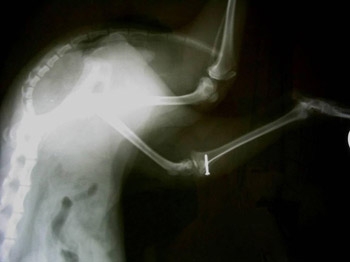

Судебно-стоматологическая экспертиза переломов челюстно-лицевых костей

Повреждения челюстно-лицевых костей среди всех травм составляют 2,5-3,8; на 10 000 городского населения приходится 2-3 такие травмы. Среди повреждений костей лицевого скелета чаще всего встречаются переломы нижней челюсти. Переломы костей лицевого скелета могут быть частичными и полными. При частичном - линия перелома пересекает всю толщу кости, образуя трещину. При полном - линия перелома проходит через вето толщу кости, и при этом костные отломки могут соприкасаться, удерживаемые ...